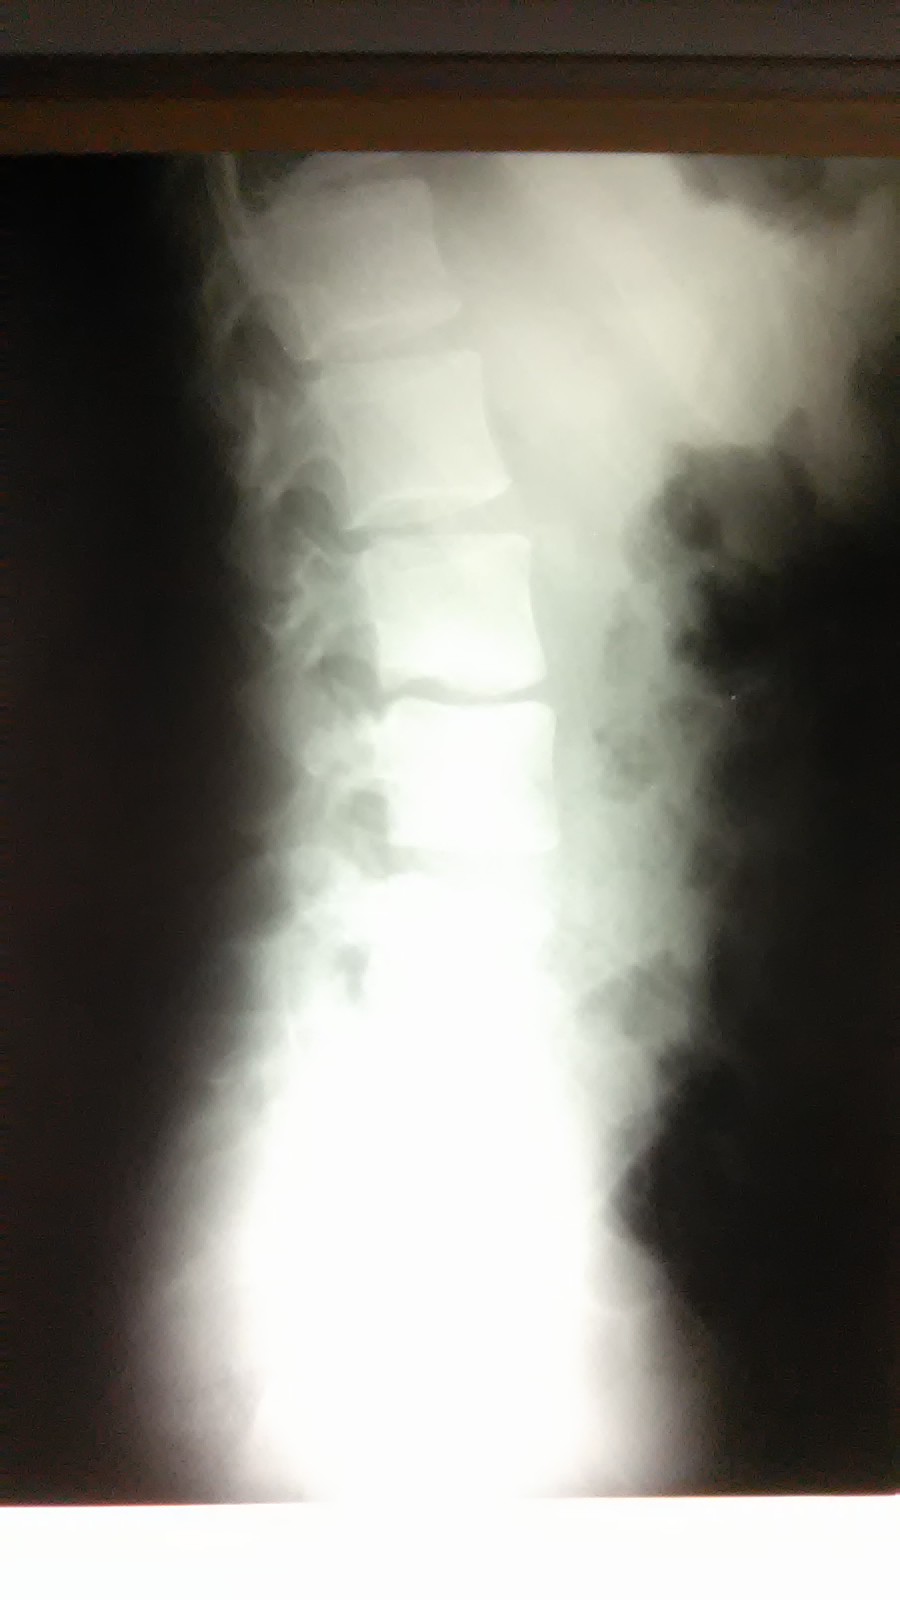

Хотел, видимо, с гнойником разобраться, но его не нашел. Что конкретно делал не знаю. Сегодня пациенту сделали Rtg.

Вложения

WP_20160627_002.jpg

WP_20160627_003.jpg

WP_20160627_004.jpg

Вот только добралась до истории болезни с описанием Rtg-снимков и заключением : "R-признаки спондилита на уровне L3-L4 с краевой деструкцией нижне-правого угла L3. Паравертебральный натечный абсцесс справа?".

Пациента записали на КТ.